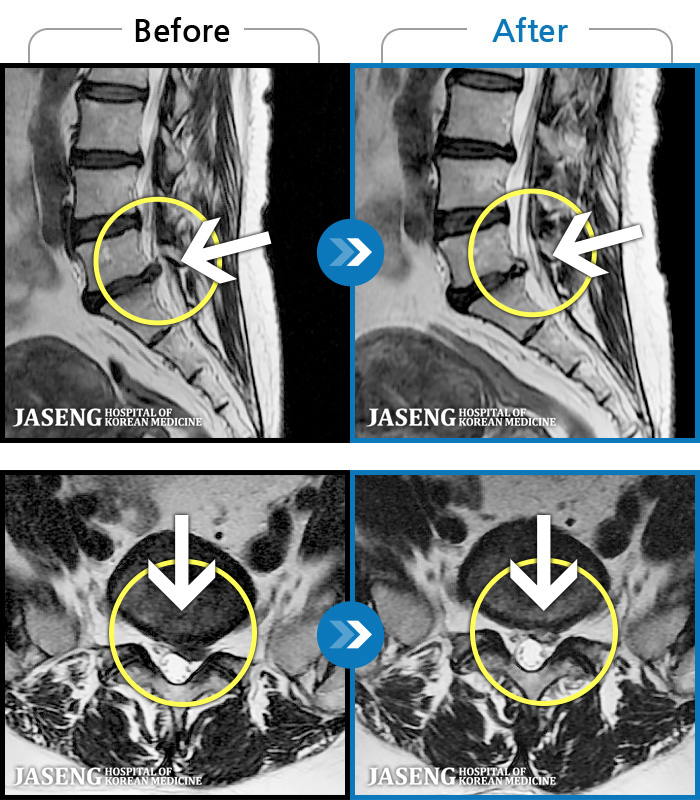

- MRI ġ

MRI ġ

1,304 MRI ũ ʸ Ȯϼ.

Ƹ ϰ ־.